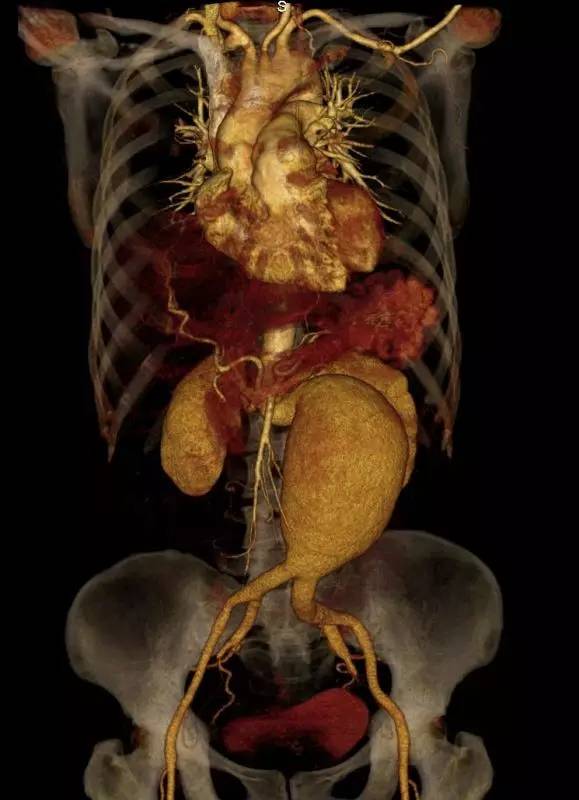

CT血管造影(CTA)

能观察主动脉瘤及内脏动脉的情况,并对腹主动脉瘤的瘤颈、瘤体以及髂动脉等远端大动脉等进行观察和测量,对于破裂腹主动脉瘤能看到破裂口和腹膜后血肿。因此CTA是诊断和治疗腹主动脉瘤中最重要的影像学资料。